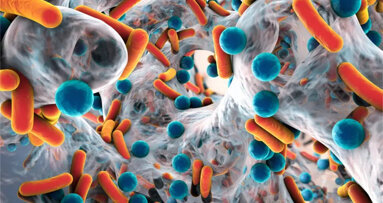

Como um dentista com mais de 40 anos de experiência, posso garantir aos meus pares que a “Guided Biofilm Therapy -GBT”, Terapia de Biofilme Guiada, é a versão atualizada da Axelsson and Lindhe’s Recall Session. Desenvolvida em colaboração com universidades e práticas odontológicas, a GBT é um conceito contemporâneo projetado para profilaxia. Com base em décadas de conhecimento científico e evidencia, a GBT é o próximo passo na prevenção.

O conceito GBT garante ama abordagem sistemática e orientado para a qualidade, cobrindo o cumprimento do paciente, de recolha de dados de diagnóstico, aconselhamento de higiene oral diária, limpeza profissional dos dentes, o diagnóstico final do dentista e check-ups, e remoção química de placa, bem como retornos. Juntamente com a revelação do biofilme supragingival, o processo profissional de limpeza de dentes mudou consideravelmente desde o trabalho de Axelsson e Lindhe.

As oito etapas que compõem a GBT podem ser adaptadas para o tratamento, desde terapia inicial até o tratamento de manutenção. A GBT é para pacientes sadios e para pacientes com cárie dentária (especialmente nas fases iniciais), gengivite, periodontite, mucosite peri-implante ou peri-implantitis.

Esta abordagem contemporânea começa com remoção de biofilme sub e supragingival utilizando a tecnologia de polimento a ar AIRFLOW PLUS Powder. Este pó com base de eritritol garante a remoção do biofilme direcionada, gentil, com risco orientado, para apoiar o diagnóstico inicial. Isto é seguido por remoção minimamente invasiva do acúmulo mineralizado com PIEZON NO PAIN. Esta abordagem tem muitos benefícios adicionais, incluindo tempos de tratamento curto e máximo conforto para o técnico e o paciente.